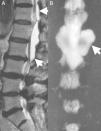

Clinical caseA 67-year-old male with a history of type 2 diabetes mellitus and lower back pain irradiating to both legs, predominantly the right, neurogenic claudication of both legs and weakness in both feet for 15 months. Physical examination revealed hypoesthesia in the right L5 dermatome, increased myotatic reflexes in both legs with Babinski sign and 4/5 power in the psoas and quadriceps bilaterally. Central and lateral stenosis of the spinal canal could be seen on magnetic resonance imaging at lumbar level from L3-L4, L4-L5, as well as the presence of a cystic lesion with regular limits, from T12 to L2. The lesion was hypointense in T1-weighting and hyperintense in T2-weighting, characteristically homogeneous with the cerebrospinal fluid; no contrast enhancement was observed on the MRI (Fig. 1). The compression of the conus medullaris and the dural sac was notable in T12-L1 and L1-L2 respectively and bilateral foraminal stenosis (Fig. 2), at the same levels due to expansion of the cyst. Given these signs, we decided to perform an evacuatory lumbar puncture targeting the spinal extradural cyst in space L1-L2 guided by fluoroscopy (Fig. 3), in order to decompress the nerve elements on which the cyst had an expansive effect. After the procedure, the patient's myelopathic syndrome improved, he had normal osteotendinous reflexes in both legs, and there were no bilateral Babinski reflexes. However, the patient continued to have neurogenic claudication and radicular pain in both legs, therefore one month after the evacuatory puncture a minimally invasive approach with microscope and tubular retractor system was undertaken through the midline for segments L3-L4 and L4-L5, and the narrow lumbar canal was decompressed. This achieved complete improvement of his symptoms.